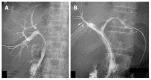

Hilar cholangiocarcinoma is a common malignant tumor of the biliary tree. It has poor prognosis with very low 5-year survival rates. Various imaging modalities are available for detection and staging of the hilar cholangiocarcinoma. Although ultrasonography is the initial investigation of choice, imaging with contrast enhanced computed tomography scan or magnetic resonance imaging is needed prior to management. Surgery is curative wherever possible. Radiological interventions play a role in operable patients in the form of biliary drainage and/or portal vein embolization. In inoperable cases, palliative interventions include biliary drainage, biliary stenting and intra-biliary palliative treatment techniques. Complete knowledge of application of various imaging modalities available and about the possible radiological interventions is important for a radiologist to play a critical role in appropriate management of such patients.We review the various imaging techniques and appearances of hilar cholangiocarcinoma and the possible radiological interventions.